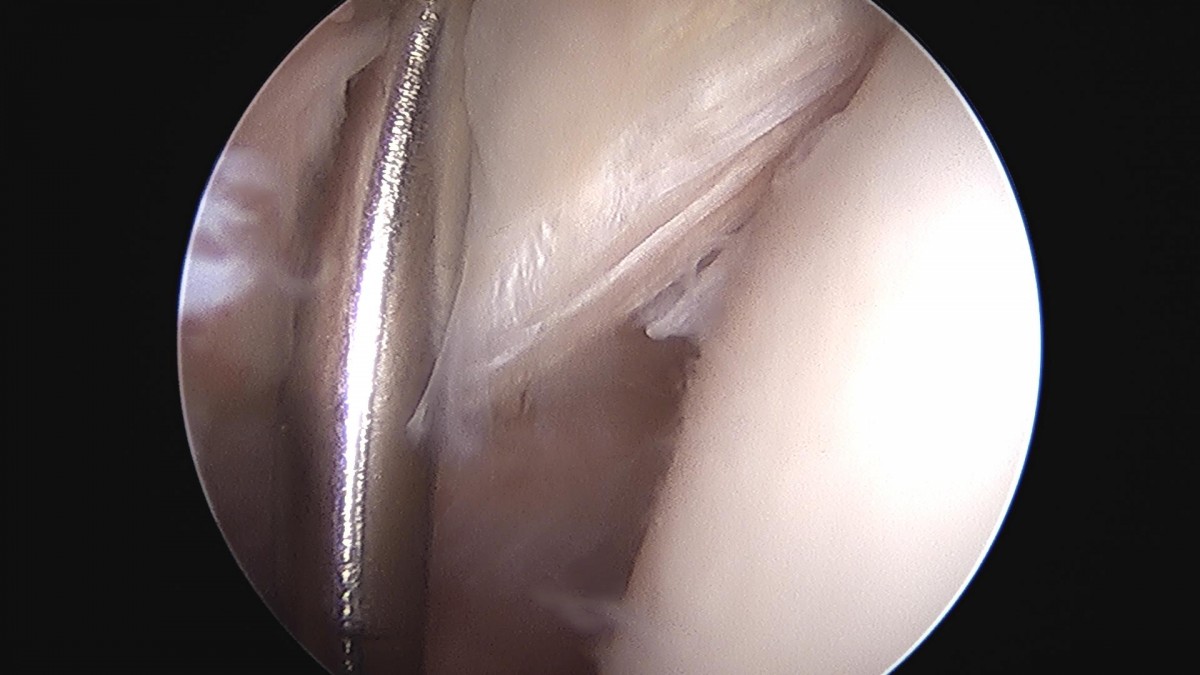

이재상원장님 어깨 회전근개 봉합술 김순O 환자

작성자 최고관리자 댓글 0건 조회 1,690회 작성일 24-10-16 16:23